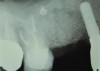

Patient 2: A 63-year-old healthy male patient presented with implant No. 6 exhibiting RPI, having been affected by previously endodontically treated and fractured tooth No. 5 (Figure 3 and Figure 4). The implant had probing depths ranging from 4 mm to 10 mm (Table 1) with the most severe bone loss at the distal aspect of implant No. 6 (Figure 3 and Figure 4).

Fig 3 and Fig 4. Case 2: Initial clinical presentation showing implant No. 6 with RPI, having been impacted by fractured tooth No. 5 (Fig 3); radiograph showing fractured tooth No. 5 with periapical lesion extending to the distal aspect of implant No. 6 (Fig 4).

Fig 4. Case 2: Initial clinical presentation showing implant No. 6 with RPI, having been impacted by fractured tooth No. 5 (Fig 3); radiograph showing fractured tooth No. 5 with periapical lesion extending to the distal aspect of implant No. 6 (Fig 4).